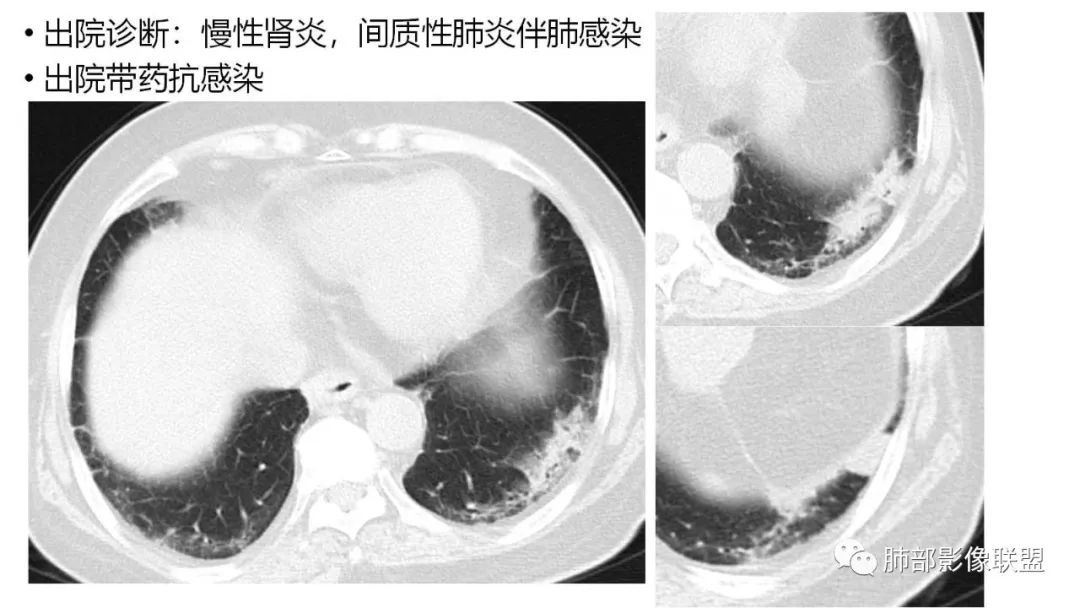

三、本例是一个误诊多年的病例,给我们很多启示:

1.多学科探讨的重要性:肾内科忽视肺部病变,后续需要呼吸、影像、病理共同探讨。

2.粘液腺癌易伪装成肺炎的形态,尤其是当患者本身具有免疫色彩的时候,易误诊为间质性肺炎,或肺部感染。若治疗无效,取得病理很重要。

4.回到本例,左下肺病变两次好转,均未经过肿瘤治疗,第一次是支气管镜后,第二次是当其他病变都在进展的情况下,左下肺病变范围反而缩小趋于浅淡。